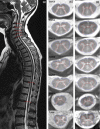

Methods: Twenty patients diagnosed with PPS (March of Dimes criteria) and 20 age- and sex-matched healthy controls (HC) underwent 3T axial 2D-rAMIRA magnetic resonance imaging at the intervertebral disc levels C2/C3-C6/C7, T9/T10 and the lumbar enlargement level (Tmax ) (0.5 × 0.5 mm2 in-plane resolution). SCGM areas were segmented manually by two independent raters. Muscle strength, self-reported fatigue, depression and pain measures were assessed.

Results: Post-polio syndrome patients showed significantly and preferentially reduced SCGM areas at C2/C3 (p = 0.048), C3/C4 (p = 0.001), C4/C5 (p < 0.001), C5/C6 (p = 0.004) and Tmax (p = 0.041) compared to HC. SCGM areas were significantly associated with muscle strength in corresponding myotomes even after adjustment for fatigue, pain and depression. SCGM areaTmax together with age and sex explained 68% of ankle dorsiflexion strength variance. No associations were found with age at or time since infection. Patients reporting PPS-related decline in arm function showed significant cervical SCGM atrophy compared to stable patients adjusted for initial disease severity.